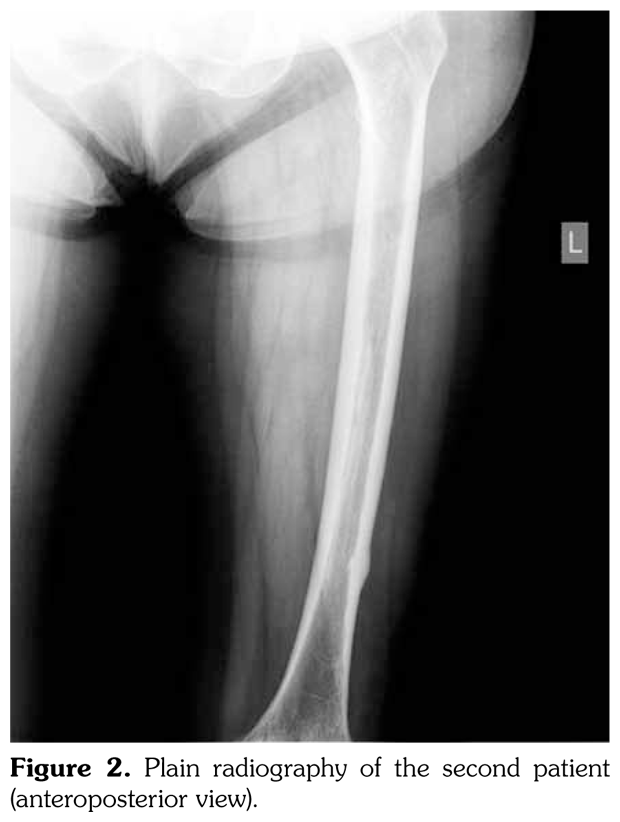

Case 2– A 61-year-old female patient presented with anterior thigh pain and difficulty in walking. Pain severity was 7 over 10 point according to visual analog scale. She had been treated with alendronate 70 mg per week with calcium plus vitamin D for two years. Plain radiographs of femur were taken upon clinical presentation. Cortical stress reaction was detected in both femoral shafts on plain radiographs (Figure 2). Computed tomographic imaging was performed to rule out fracture (Figure 3). Bone scintigraphy showed increased uptake in distal (1)/3 ends of femoral shafts (Figure 4). Serum calcium value was normal and urinary deoxypiridinoline level was mildly increased (46 nM/mMCre).